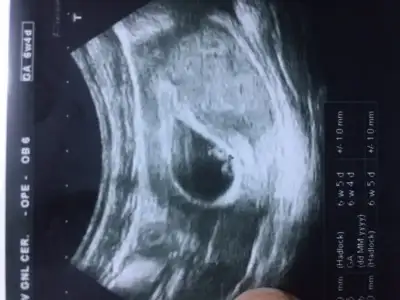

Banada yorum yaparmsnz burada bebegim 8+4 sali gunu cinsiyetini ogrenecegz ama dogru cikacakmi merak ediyor bioritim icin de benim

Dün bir saat boyunca okudum burayı ve kızımın usg resmine baktım sağdaydı gerçekten çok şaşırdım:) şimdi 5.haftaya giriyorum keseyi gördük 2 hafta sonra bebek belli olacakmış heyecan yaptım karşılaştırmak için sabırsızlanıyorum ama çok yoğun bir şekilde kız hissediyorum yine:))